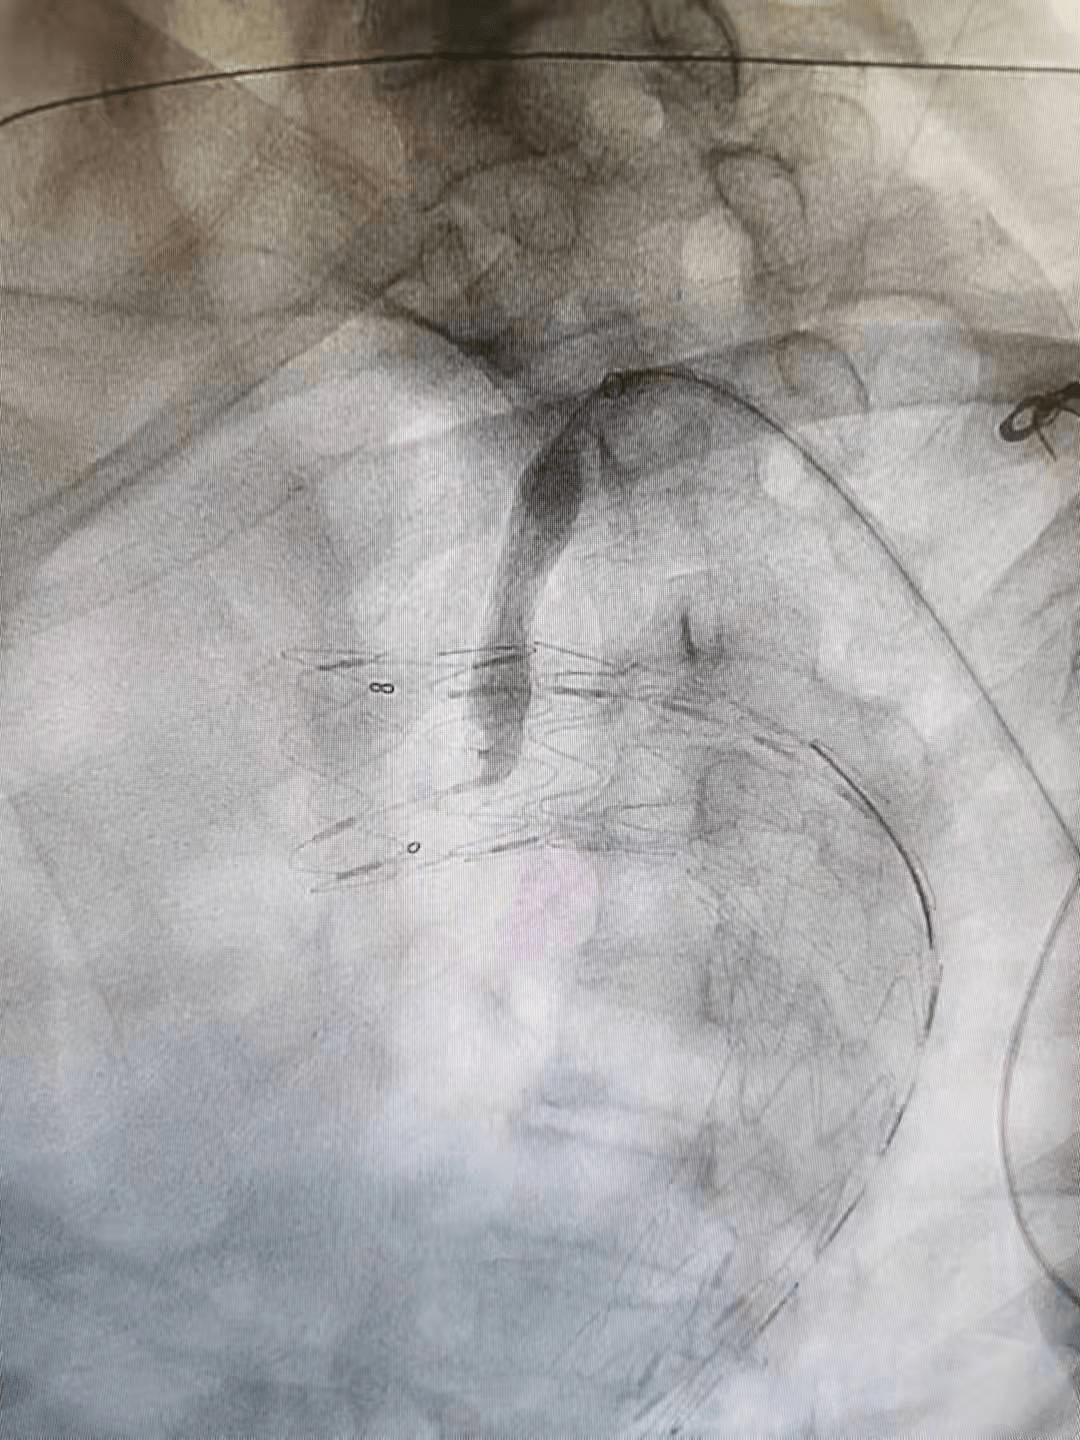

在介入手术室王素娟护士长和付晓慧、陈浩等护士积极配合下 , 刘洪主任带领潘仲杰和郑鹏远两位医生 , 沿患者右侧股总动脉造影(见图二、图三)置入胸主动脉覆膜支架 , 于左颈总动脉的左侧缘 , 先覆盖左侧锁骨下动脉 , 再经左肱动脉进行穿刺 , 用可调弯鞘在左锁骨下动脉开口处体内原位开窗(见图四) , 经球囊扩张窗口(见图五) , 置入球扩覆膜支架(见图六) , 保证了患者主动脉及左锁骨下动脉血流 。

(图三)